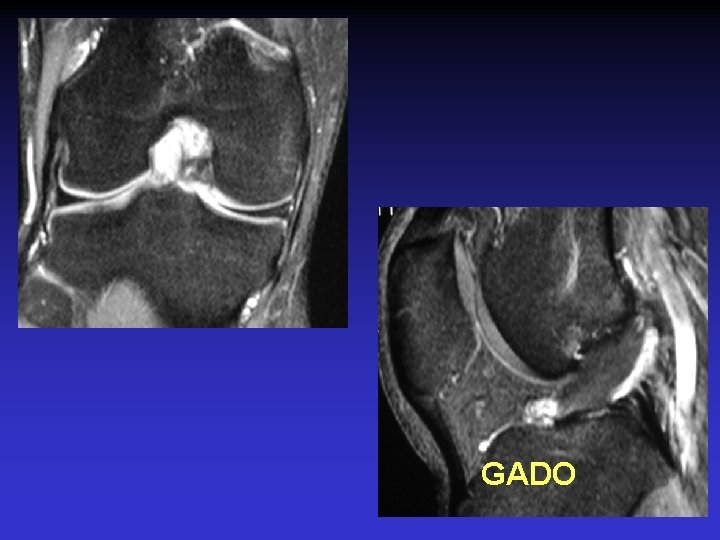

ASPECT IRM • • Hyposignal TI Hypersignal T 2 Pas de prise du contraste après Gado IV Continuité conservée du LCA+++ avec dilacération des fibres • Aspect en « tige de céleri »

GADO

GEODES SYNOVIALES • En regard des zones d’insertion fémorale et / ou tibiale • Hypo TI Hyper T 2 • Rehaussement possible après Gado IV